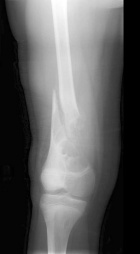

C.L. - 12 year old white male who fell while playing football in his backyard, sustaining an injury to his right leg

Zoom image: Radiological image Radiological image.